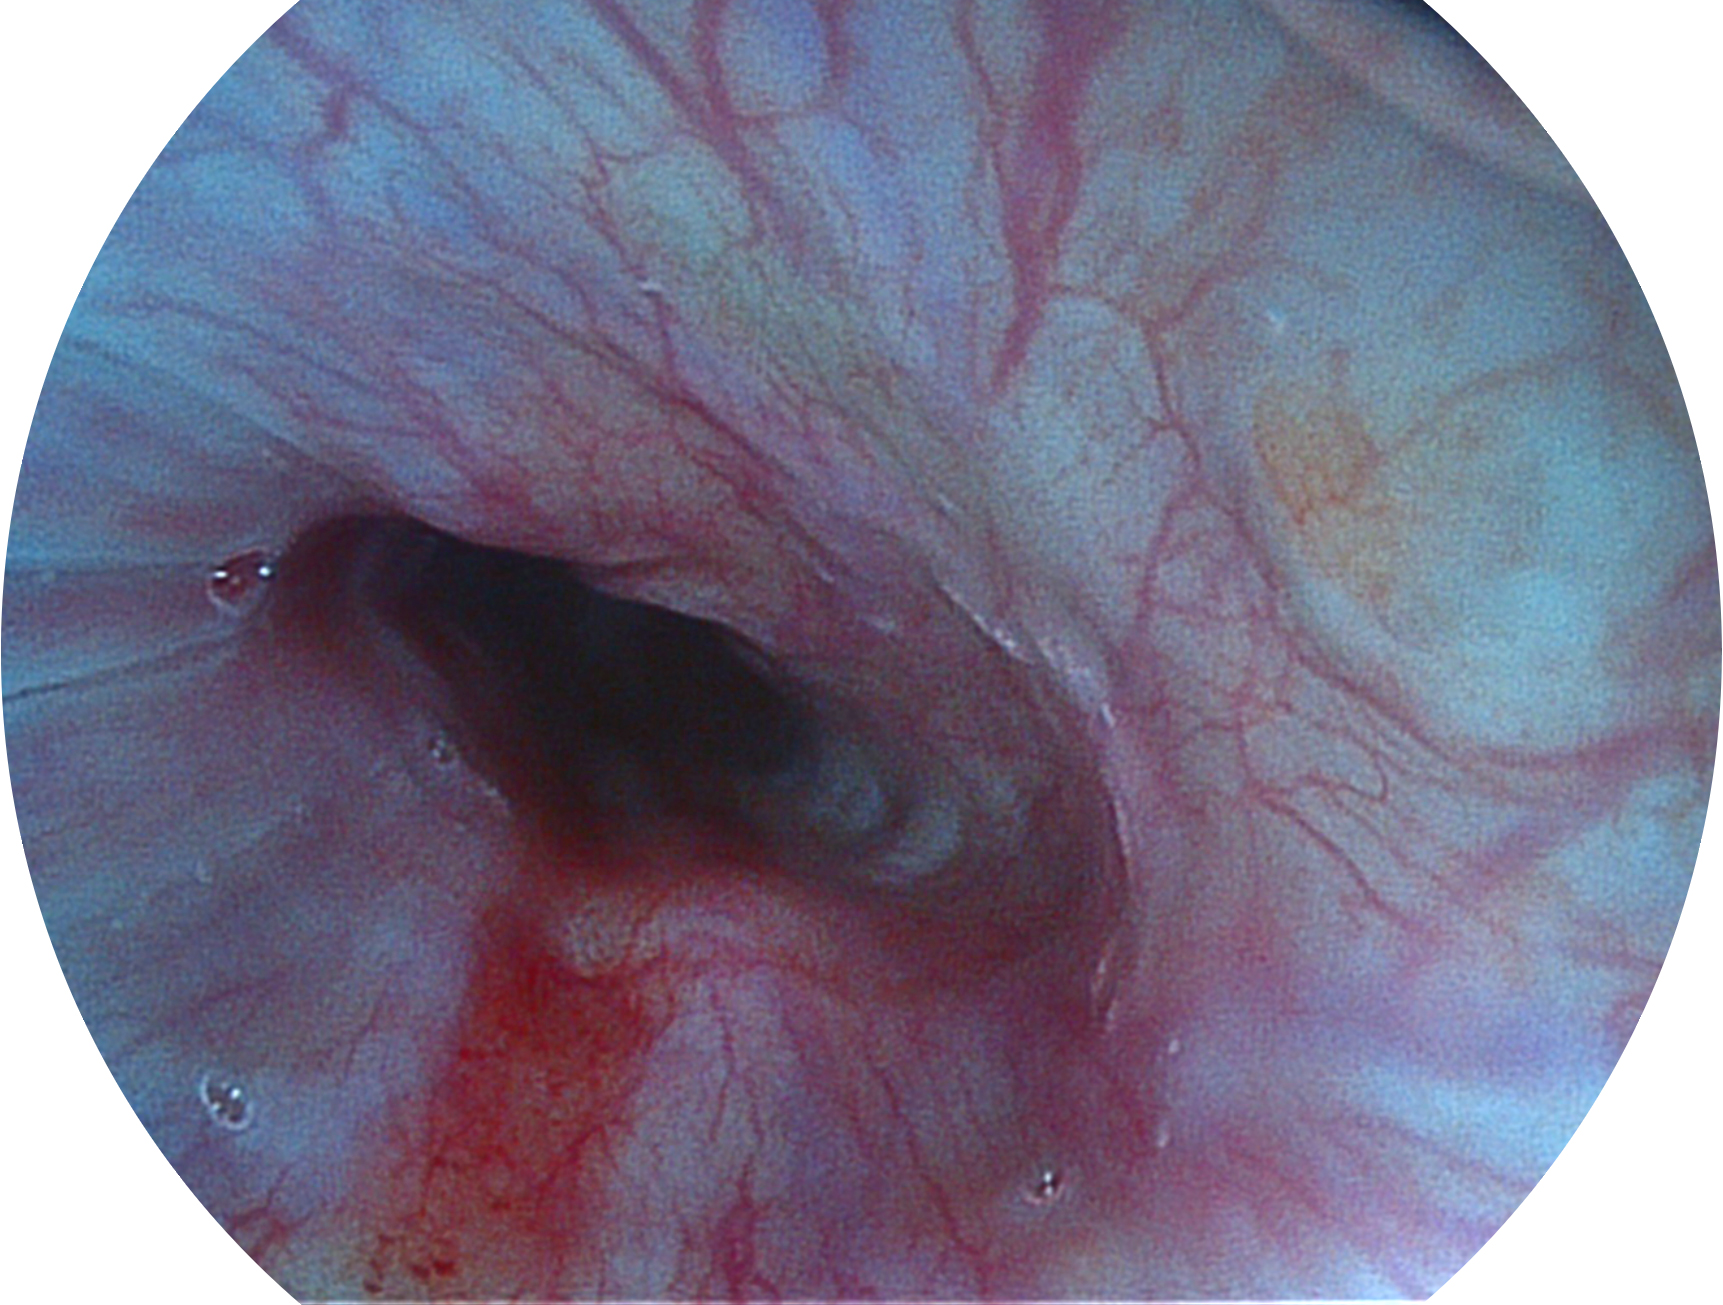

狗万官方网站新开发的内镜染色技术,主要是基于多波长LED 光源的开发,VLS-55Q 四波长LED 光源是由四个不同颜色的LED光按照相应照明模式所规定的特定发光比例进行合束后形成,合束后形成的照明光的光谱由红光、绿光、蓝光及蓝紫光这四个不同的波段范围构成。具有更高光谱自由度,通过光谱比例的控制,实现了聚谱成像技术,英文全称为“Spectral Focused Imaging, SFI”,缩写为“SFI”和光电复合染色成像技术,英文全称为“Versatile Intelligent Staining Technology, VIST”,缩写为“VIST”。